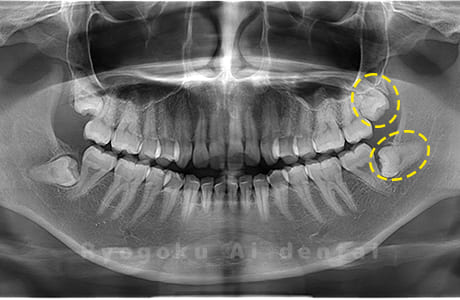

Case04

- 原因

- 上顎の親知らず、下顎の水平埋伏の親知らず

- 治療内容

- 上顎の親知らず、下顎の水平埋伏の親知らずを抜歯したケースです。

<リスク・副作用>

手術後は痛み、腫れ、痺れなどの副作用が生じる場合があります。